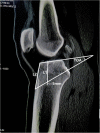

Methods: The measurements were performed on CT sagittal plane, including the thickness of cancellous bone (L1), the theoretical optimal angle of the tibial tunnel (TOA, which was measured between tibial plateau and the extension cord connecting the center of PCL insertion site with a point 5 mm superior from marrow cavity vertex), L2 - the distance from anterior tunnel aperture to anterior end of tibial plateau, L3 - the distance from anterior tunnel aperture to tibial tuberosity (lowest edge of patellar ligament attachment).

Results: The value of TOA and L3 were 35.4 ± 7.9 ° and 26.8 ± 11.4 mm, respectively. L1 and L2 were higher in males than females (L1, P = 0.002; L2, P = 0.046). Regarding age, L1, TOA, L2 and L3 were higher in the 46-60 years group than 31-45 years group (P = 0.02, P = 0.001, P = 0.038, P = 0.032, respectively). With regard to height, L1 was lower in group I - < 1.66 m than group II - 1.66 to 1.75 m and group III - > 1.75 m (I v II, P = 0.015, I v III, P = 0.026). L2 was also lower in group I than group II and group III (I v II, P = 0.026, I v III, P = 0.006). TOA and L3 showed no significant differences among sex and height groups (P > 0.05).

Conclusions: TOA (35.4 ° ± 7.9 °) and L3 (26.8 ± 11.4 mm) could be used as a reference for ideal tibial tunnel placement in transtibial anatomic PCL reconstruction, so as to prevent recurrent PCL laxity and ensure good graft healing. However, further clinical validation is needed.